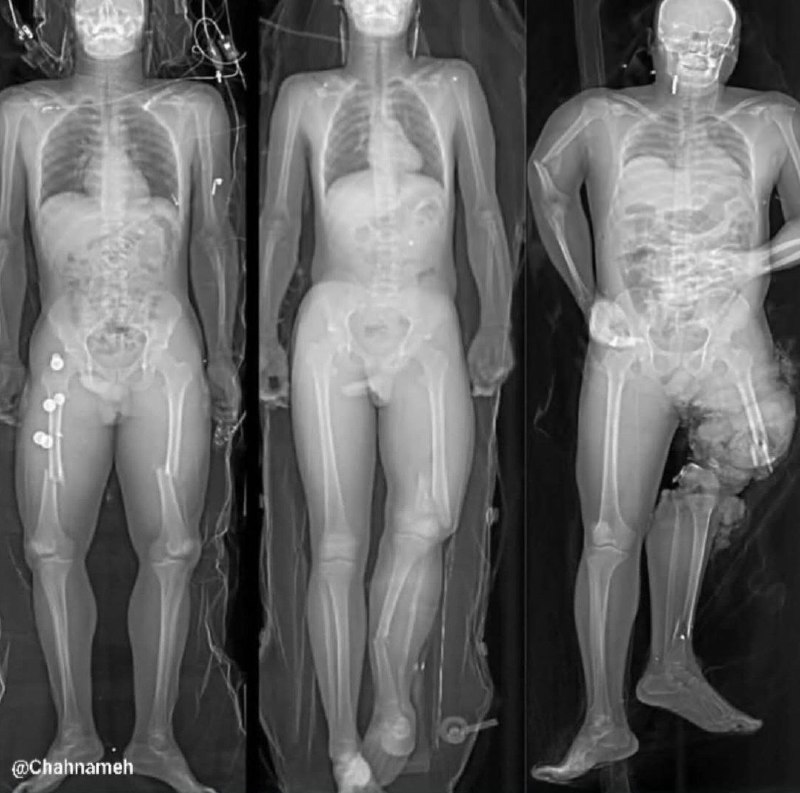

⚠️ نامناسب برای همه، اگه حساس هستید زوم نکنید!

۳ نفر توی یک تصادف بودن. هیچ‌ کدوم کمربند نبسته بودن، اما تفاوت اصلی در نوع نشستن‌شون در خودرو بوده.

نفر سمت چپ موقع تصادف پاهاشو روی هم گذاشته بود. وقتی ضربه وارد شده، بدنش پیچ خورده و استخوان‌های پا